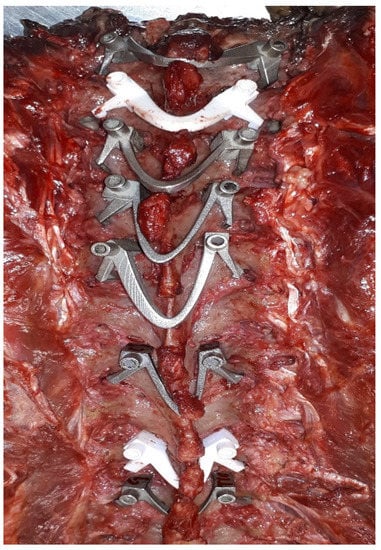

4. Clinical Application